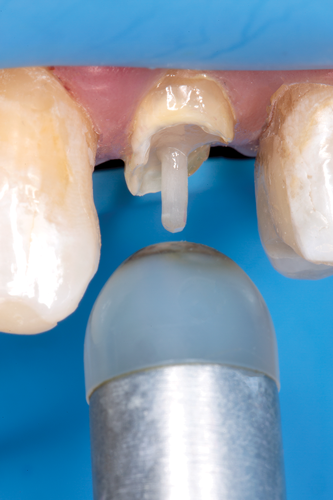

The preselected fiber-reinforced composite post was placed into the channel space, and the coronal height was measured and marked (Figure 12). The post was cleaned with alcohol, and its surface was silanated with a ceramic primer and air-dried after 60 seconds. The prepared channel was cleaned with a 2% chlorhexidine solution, rinsed, and dried with an endodontic paper point. The prepared endodontic channel was then etched for 15 seconds with 37.5% phosphoric acid semigel. The gel was agitated in the post channel with a paper point (Figure 13), rinsed for 5 seconds, and dried with an endodontic paper point without dehydrating the dentin structure. A universal adhesive was applied with an applicator brush onto the walls and base of the channel and air-dried (Figure 14); any excess adhesive was absorbed with an endodontic paper point using a rapid intermittent movement. The adhesive was lightly air-thinned using a warm air tooth dryer and light-cured for 40 seconds. An injectable flowable universal resin composite was injected into the post channel using an angled tip (Figure 15). It is important to remove the tip slowly while injecting to prevent the incorporation of air bubbles. The aforementioned fiber post was immediately inserted into the post space to the base of the prepared channel, and light-curing was performed from different positions (ie, coronal, facial, and lingual) for 2 minutes (Figure 16).

Fig 15. Flowable resin composite injected into the post channel using an angled tip.

Figure 15